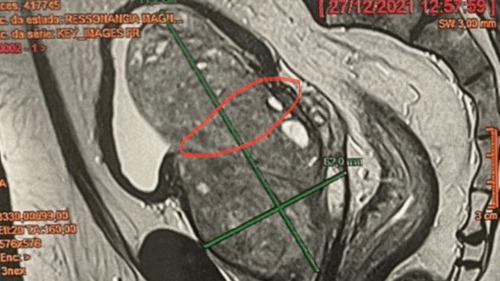

A hiperplasia prostática benigna (HPB) é uma condição muito comum entre os homens à medida que envelhecem, e não está associada ao câncer de próstata, mas pode causar sintomas urinários incômodos e afetar seriamente a qualidade de vida. Estima-se que cerca de 50% a 75% dos homens com 50 anos ou mais apresentem HPB; em idosos acima de 70 anos, esse número pode chegar a 80%.

Diante desse cenário, surge a HoLEP (Holmium Laser Enucleation of the Prostate): uma técnica avançada, minimamente invasiva, que utiliza laser de alta potência para remover o tecido prostático que bloqueia o fluxo urinário. O objetivo é oferecer alívio dos sintomas, menos complicações e recuperação mais rápida.

A técnica é indicada para homens com sintomas urinários moderados a graves, inclusive em próstatas muito volumosas. “É um procedimento seguro e eficaz, que proporciona alívio definitivo na maioria dos casos”, reforça.

O HoLEP pode ser realizado em próstatas de qualquer tamanho, sem limite superior. As contraindicações são mais relacionadas ao estado geral de saúde do paciente: doenças cardíacas ou pulmonares graves, infecção urinária ativa ou risco anestésico elevado exigem avaliação específica.